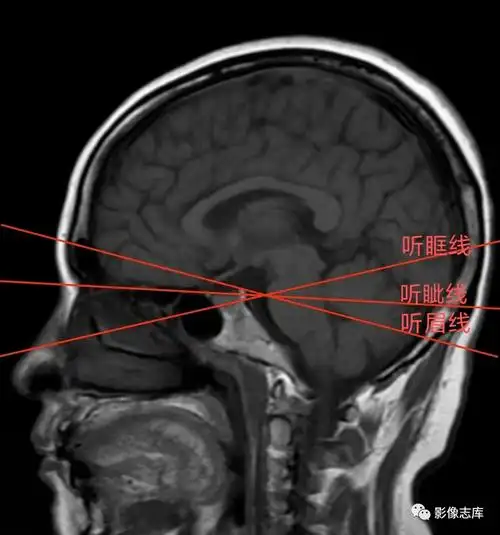

头颅ct扫描时如何打角度才能看得更多更清晰